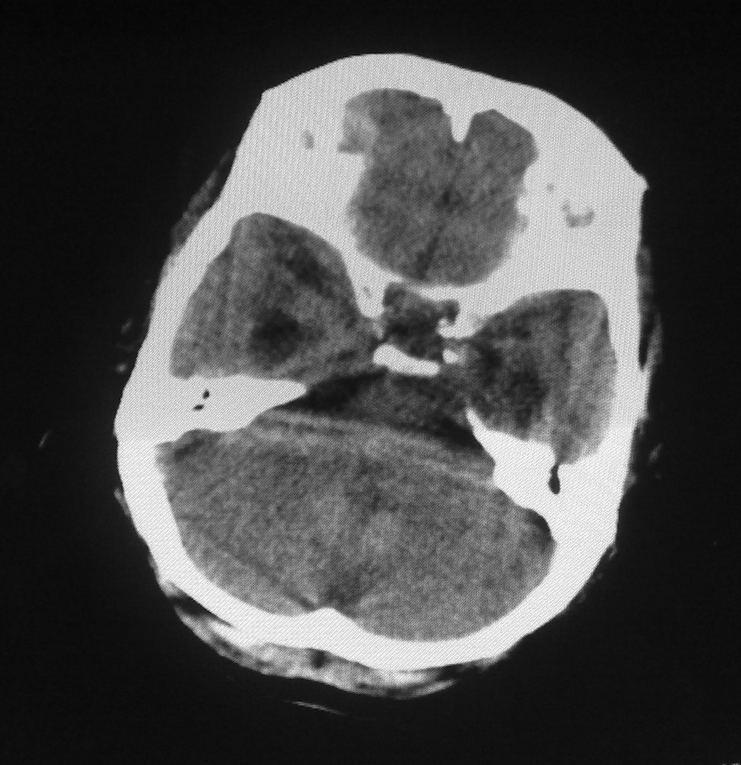

男,61岁,发热,有脑出血病史。

右侧基底节,放射冠软化灶,胼胝体发育不良 脑积水原因待查。

脑积水【脑室血块阻塞?】

脑积水!四脑室显示不清,导水管梗阻?建议mri!

右侧基底节及放射冠软化灶,脑积水,四脑室显示不清,导水管梗阻?建议mri!

梗阻性脑积水,出血后粘连所致

1)右侧基底节区、右侧放射冠及右侧丘脑软化灶。2)脑积水。